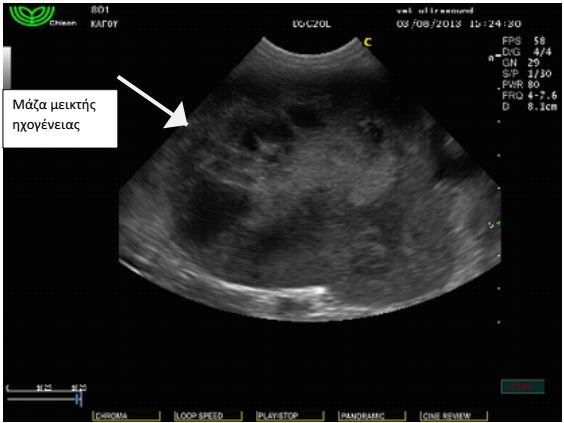

Στον υπέρηχο κοιλίας βρέθηκε μάζα σπηλαιώδης, η οποία

ξεκινούσε από τον σπλήνα και καταλάμβανε μέρος της πρόσθιας

κοιλίας καθώς και παρουσία ασκητικού υγρού. Το ήπαρ φαινόταν

φυσιολογικό χωρίς απώλεια της δομής και του σχήματός του.